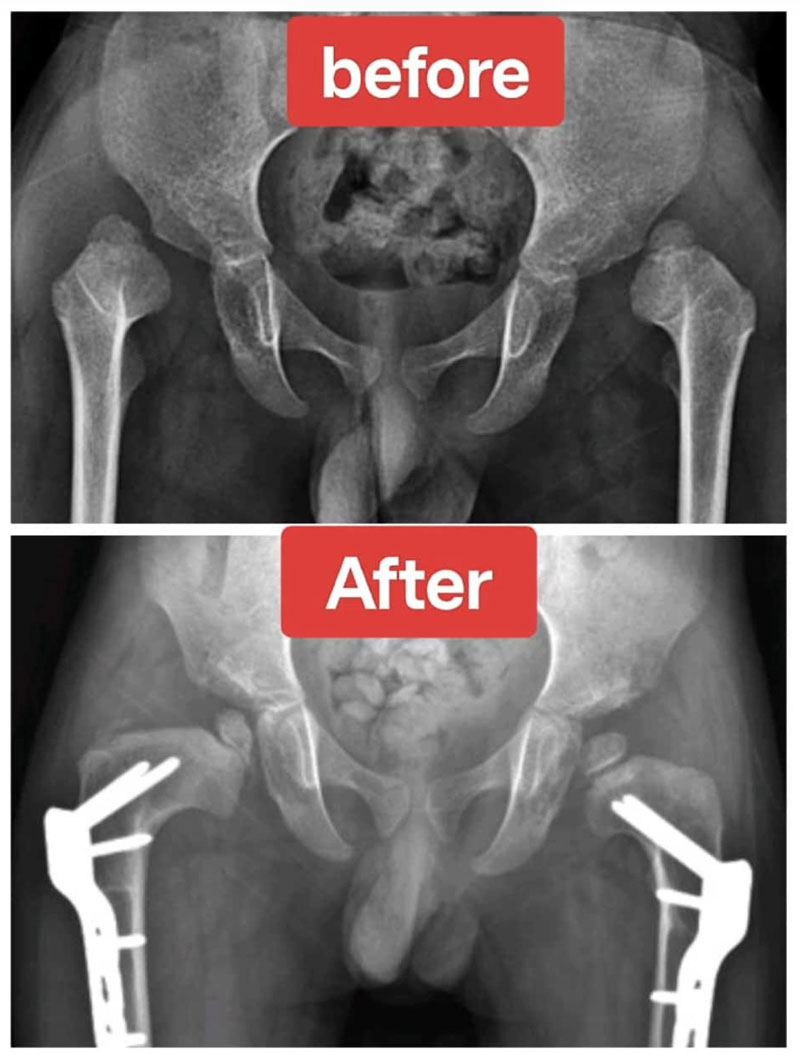

Hip Preservation Surgery